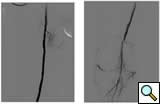

Case 3: An 81-year-old male with rest pain. The patient underwent angiography via an antegrade approach, which revealed extensive

![]() |

| Figure 3A |

| Figure 3B |

| Figure 3C |

calcific lesions of the superficial femoral artery (Figure 3A) and a lesion in the tibio-peroneal trunk (Figure 3B). The SFA lesions were debulked with a laser and the patency restored with Viabahn stents (Figure 3C). The tibio-peroneal represented the sole run off and was left as we were worried about creating a disaster if the lesion ruptured or dissected. ABI increase from 0.19 pre-procedure to 0.55 post and the patient is now able to ambulate with manageable claudication. Options to treat the more distal lesion could involve using a distal protection device and coronary balloons and/or stents.